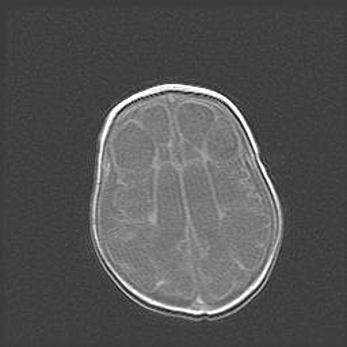

Открытая гидроцефалия.

Возраст: 9 месяцев 12 дней

Вес: 6800 г

Пол: мужской

Окружность головы: 41,5 см

Срок гестации: 28 недель

Гидроцефалия головного мозга у новорожденных имеет характерный признак: опережающий рост окружности головы приводит к визуально хорошо определяемой гидроцефальной форме сильно увеличенного в объёме черепа. Детские неврологи определяют следующие симптомы гидроцефалии у грудничков: выбухающий напряжённый родничок, частое запрокидывание головы, смещение глазных яблок к низу.